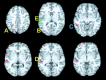

Functional magnetic resonance imaging (fMRI) was used to determine whether performance on lexical tasks was correlated with cerebral activation patterns. We found that such relationships did exist and that their anatomical distribution reflected the neurocognitive processing routes required by the task. Better performance on intramodal tasks (determining if visual words were spelled the same or if auditory words rhymed) was correlated with more activation in unimodal regions corresponding to the modality of sensory input, namely the fusiform gyrus (BA 37) for written words and the superior temporal gyrus (BA 22) for spoken words. Better performance in tasks requiring cross-modal conversions (determining if auditory words were spelled the same or if visual words rhymed), on the other hand, was correlated with more activation in posterior heteromodal regions, including the supramarginal gyrus (BA 40) and the angular gyrus (BA 39). Better performance in these cross-modal tasks was also correlated with greater activation in unimodal regions corresponding to the target modality of the conversion process (i.e., fusiform gyrus for auditory spelling and superior temporal gyrus for visual rhyming). In contrast, performance on the auditory spelling task was inversely correlated with activation in the superior temporal gyrus possibly reflecting a greater emphasis on the properties of the perceptual input rather than on the relevant transmodal conversions.